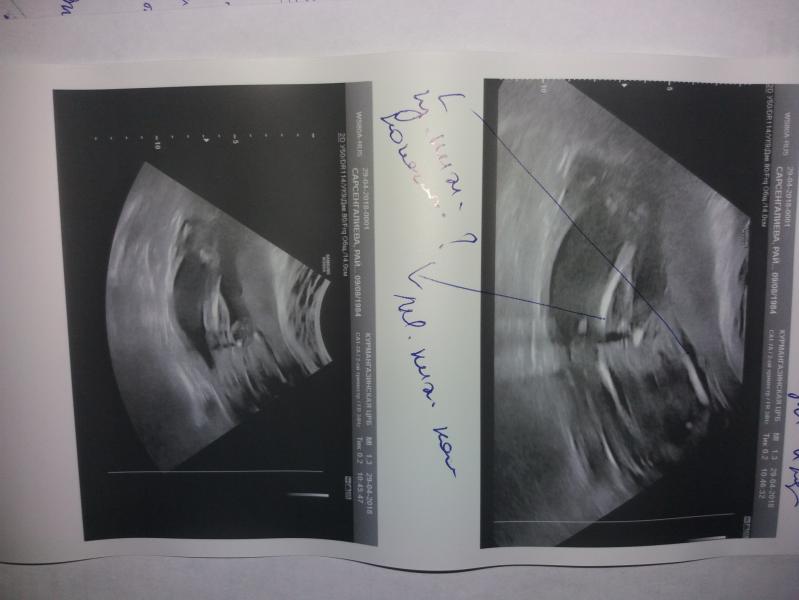

Угроза прерывания изо тонуса по задней стенке матки,беременность 22-23 недели.на момент осмотра правый коленный сустав в развернутом виде,иследовать не удается.рекомендовано дообследование узи плода дабы исключить костно-суставную патологию конечностей плода справа

Упб- угроза прерывания беременности . Беременность 22-23нед. Рек-но узи плода исключить костно-суб....что-то там